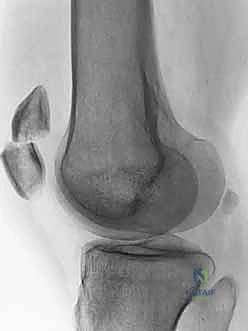

* Bipartite patella: This developmental anomaly, resulting from failed fusion of ossification centers, can be mistaken for a fracture. Bipartite patellae are typically superolateral, more common in males, and bilateral in 40% of cases. They have sclerotic margins, unlike acute fractures.

* Fellows, examine this image: Note the classic superolateral position and sclerotic margins of a bipartite patella.